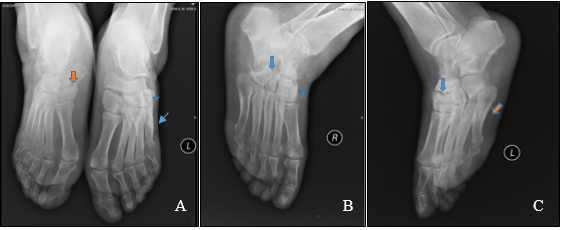

The patient did not comply with the indications given by Orthopedics and continued weight-bearing without any modification in her usual footwear nor using custom-made insoles. The patient maintained her diabetes followed-up in Internal Medicine consultation and weight-bearing radiography of the feet was performed for follow-up of progression of Charcot foot, four years later (Figure 5). Clinically, both feet demonstrated flattened plantar surfaces.

Figure 5 Weight-bearing dorsoplantar feet radiographs (A: orange star shows diffuse bony sclerosis especially seen in the right naviculocuneiform joint with remodeling; blue star shows fusion of the left cuneiform and cuboid bones and consolidated fracture of the 5th metatarsal bone); lateral image of right foot (B: disorganized tarsal and tarsometatarsal joints with unclear bone borders and diffuse remodeling; calcaneal bone absorption and bony fragments); and lateral image of left foot (C: unclear margins of the tarsal bones, diffuse sclerosis and consolidated fracture of the 5th metatarsal).